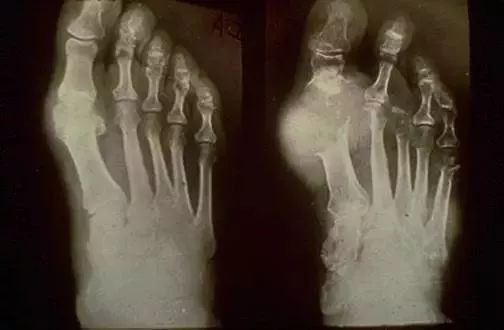

刘医生:如果真的有人这样想,医生们真的要气炸了!先看以下几张图,感受一下血尿酸偏高引起痛风带来的后果……

不要以为我们是乱找的图片吓大家,这些是真实痛风患者的照片!